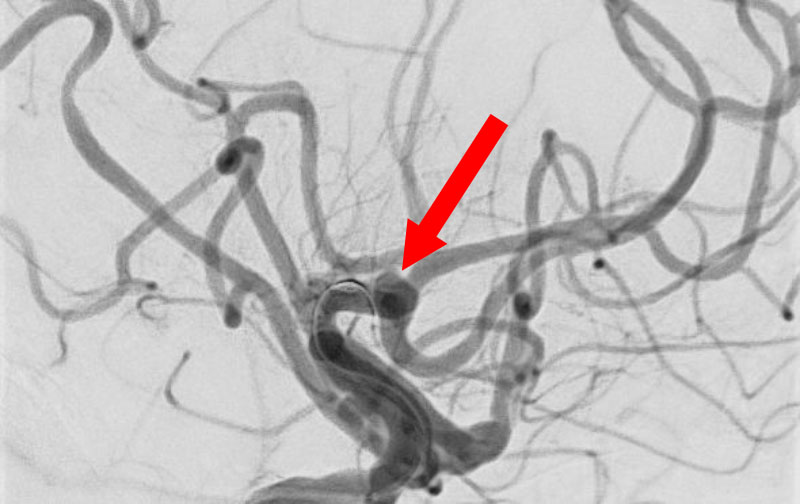

'25年11月

くも膜下出血

右内頚動脈後交通動脈

分岐部動脈瘤破裂

60代

救急外来

No.1593 手術前

No.1593 手術中

No.1593 手術後